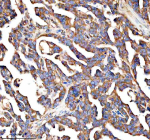

Immunohistochemical staining of PALS1 using anti-PALS1 antibody. PALS1 was detected in a paraffin-embedded section of human ovarian cancer tissue. Heat mediated antigen retrieval was performed in EDTA buffer (pH 8.0, epitope retrieval solution). The tissue section was blocked with 10% goat serum. The tissue section was then incubated with 2 ug/ml rabbit anti-PALS1 antibody overnight at 4oC. Peroxidase Conjugated Goat Anti-rabbit IgG was used as secondary antibody and incubated for 30 minutes at 37oC. The tissue section was developed using an HRP secondary and DAB substrate.